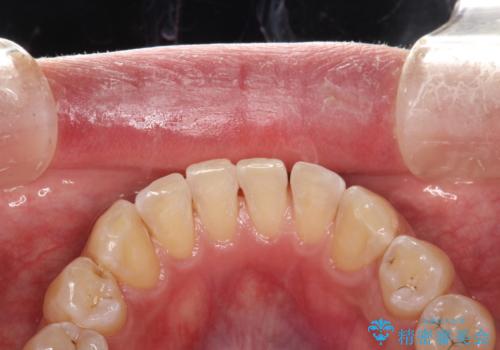

- 歯磨きの際に出血したり、口臭も気になるとのことで来院されました。PMTC30分コースにてクリーニングを行いました。

歯磨きの際の出血、お口の中の違和感・変化などを放置していると、のちに歯を失ってしまう原因になることもあります。

歯周病の原因は、口の中に棲む歯周菌です。歯周病菌や歯周病菌の出す毒素が引き起こす炎症によって歯茎が腫れ、歯を支えるセメント質、歯槽骨や歯根膜が破壊されて、ついには支えを失った歯が抜けてしまうという怖い病気です。

セルフケアだけでは、歯周病を治したり予防したりすることは困難です。

歯科医院で定期的にクリーニングを行い、歯石除去や細菌に汚染された歯根面の掃除が必要になります。